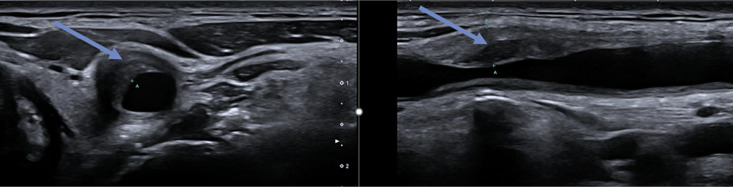

Case presentation: We narrate all reported cases of TA in patients with MS and report the case of a 57-year-old woman with MS with suspected bilateral optic neuritis and typical contrast-medium enhancement in both optic nerves. Because of normal visual acuity on both eyes, malignant hypertension, and fundoscopic findings indicative of hypertensive retinopathy, we diagnosed hypertensive retinopathy with secondary contrast-medium enhancement of the optic nerves. We established antihypertensive medication and searched for secondary causes of hypertension and highly elevated erythrocyte sedimentation rate, which led to the finding of large vessel wall inflammation and the diagnosis of TA.